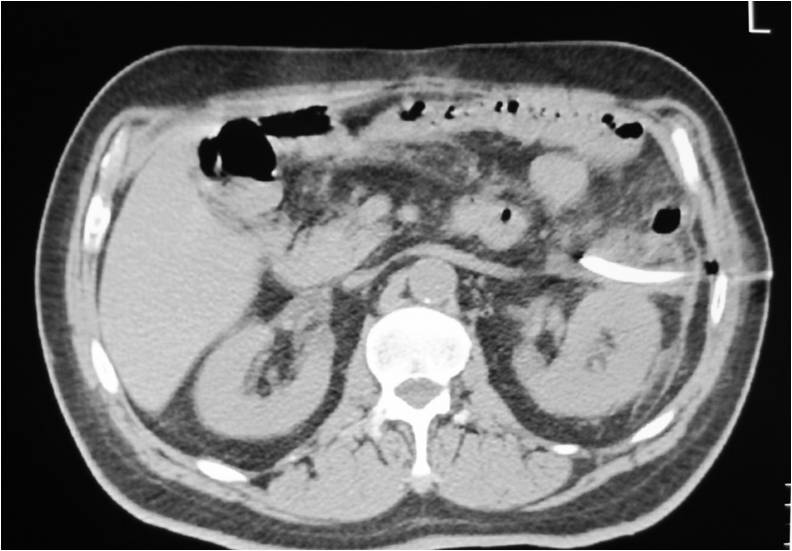

- Abscess post left hemicolectomy

- Successful placement and drainage